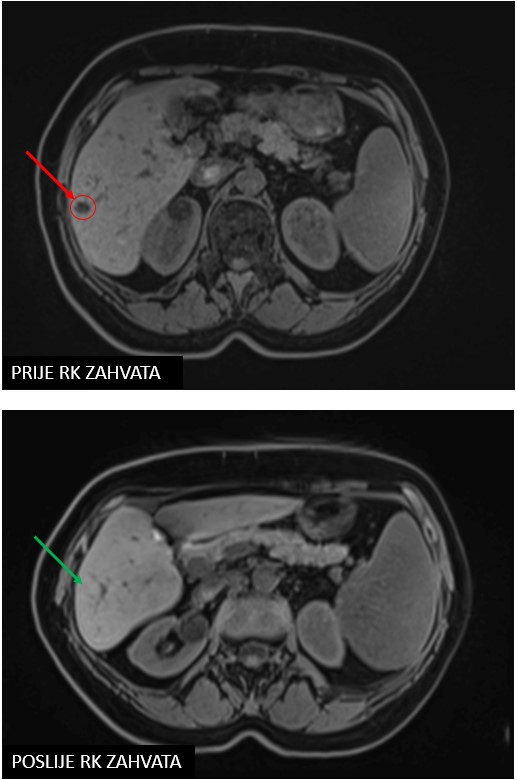

Meta hepatis

SBRT meta hepatis (07/2020, 10/2020, 06/2021, 10/2021, 06/2022)

Rezultat – 35 mjeseci nakon RK

Potpuni nestanak tretiranih lezija